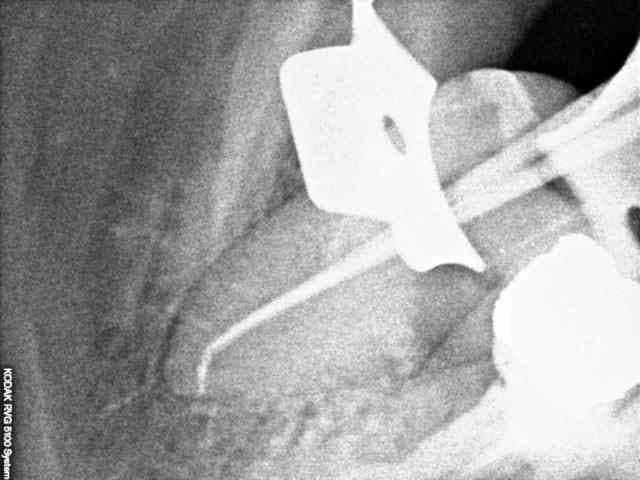

Un patient se présente avec une lésion carieuse importante sur 47. Je fait une rétroalvéolaire. La forme de l'endodonte m'interpelle, je curete et ne fait pas d'effraction pulpaire, donc je met un CVI. Le patient fait une pulpite, je fait le traitement, j'ai trouvé un très gros canal distal que je pensais unique, puis un tout petit mésial bien centré dans le sens linguo vestibulaire.

Avez vous déjà rencontré ce type de dent.

Ai-je tout obturé?